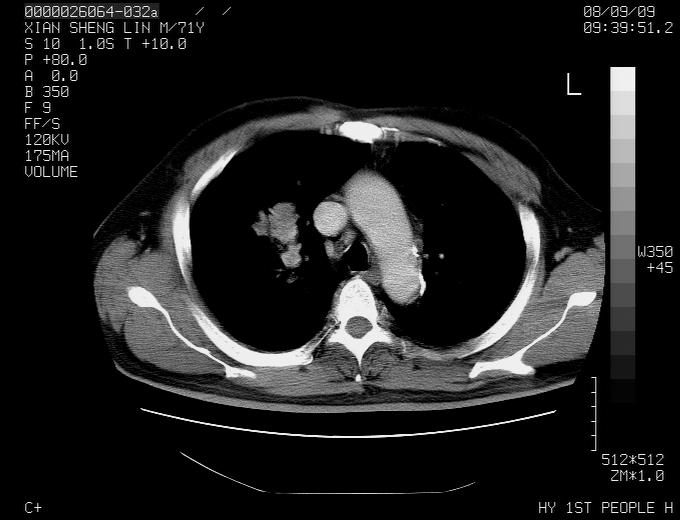

典型的右肺中心性肺癌并纵隔淋巴结转移

右肺中心性肺癌并纵隔淋巴结转移可能性大!

右肺中心性肺癌并纵隔淋巴结转移可能性大! 支持!

病灶中等程度强化 还是支持肺癌诊断

考虑右肺中心性肺癌并右肺门及纵隔淋巴结转移。

1,右肺中心型ca,气管隆突旁淋巴结转移。

支持右肺中心性肺癌并右肺门及纵隔淋巴结转移。